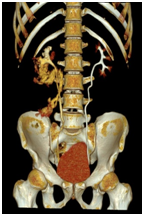

Ultrasonography of urinary system showed hydronephrosis of right kidney, calculus of right distal ureter and small perirenal effusion. Ultrasonography of digestive system showed no abnormality of liver, pancreas and spleen. There was no improvement, treated by a medical expulsive therapy for 2 days. A subsequent CTU (Computed Tomography Urography) scan showed right hydronephrosi and right lower ureteral stones 2-11 mm (Figure 1). A vast shadow of water with CT value about 2-10 HU is around the right kidney and upper ureter (Figure 2). The ureteral rupture with leakage of contrast is shown from the proximal ureter at the level of the 3rd lumbar vertebra.

Figure 2 The ureteral rupture with leakage of contrast from the proximal ureter.